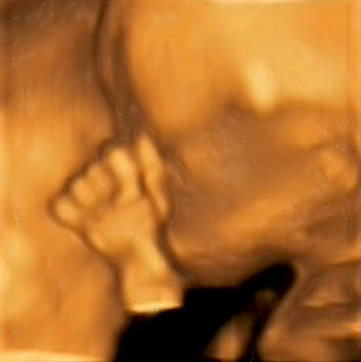

A kép egyébként egy naposan készült a kórházban, Zalánról.

Hihetetlen jó érzés a kis puha csomagot fogni, ahogy bebújik a nyakamhoz, fantasztikus érzés.